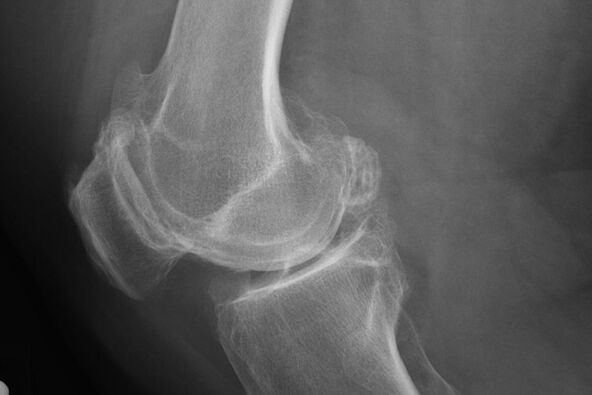

A matsayinka na mai mulkin, sakamakon cutar da cutar ta faru ta hanyar haɗari, a lokacin wani x--cray. A kan shi, likita na iya lura da wasu rashin daidaituwa kan guringuntsi. Hakanan yana yiwuwa a kunshi lumen tsakanin sassan haɗin gwiwa.

X - zai taimaka wajen gano karkacewa a guringuntsi.

Bayan jarrabawa, likita ya ba da sanarwar mai haƙuri. Wannan shine babbar hanyar gano arthrosis na gwiwa da gwiwa a kowane digiri.

X -ray yana ba da likita game da canje-canje na faruwa a cikin guringuntsi na haɗin gwiwa. Koyaya, a wasu halaye, bazai bayyana matakin farko ba a wannan hoton.

Idan ya cancanta, likita zai iya tallata maimaitawa hanyar X-ray ko lissafi da kuma tarihin goman alade.